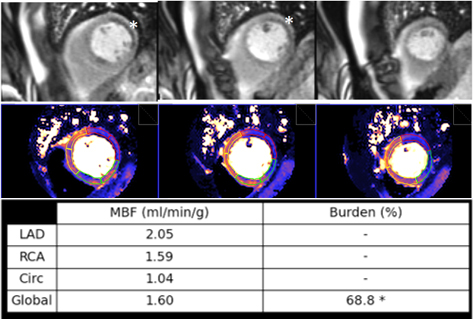

Multivessel disease is a scenario where the diagnostic performance of perfusion

Fig. 35.Ischemic burden in multiple vessel disease as assessed by QP. Stress perfusion (top row) showing a marked defect at the lateral wall (asterisks) while the assessment of the rest of segments is uncertain. Derived from the perfusion mapping (middle row), and assigned to coronary territories, are values of MBF (bottom row) indicating significant inducible ischemia for the territory of the circumflex artery, clear impairment of the RCA, and mostly preserved LAD region, all accounting for a global ischemic burden of 68.8%.